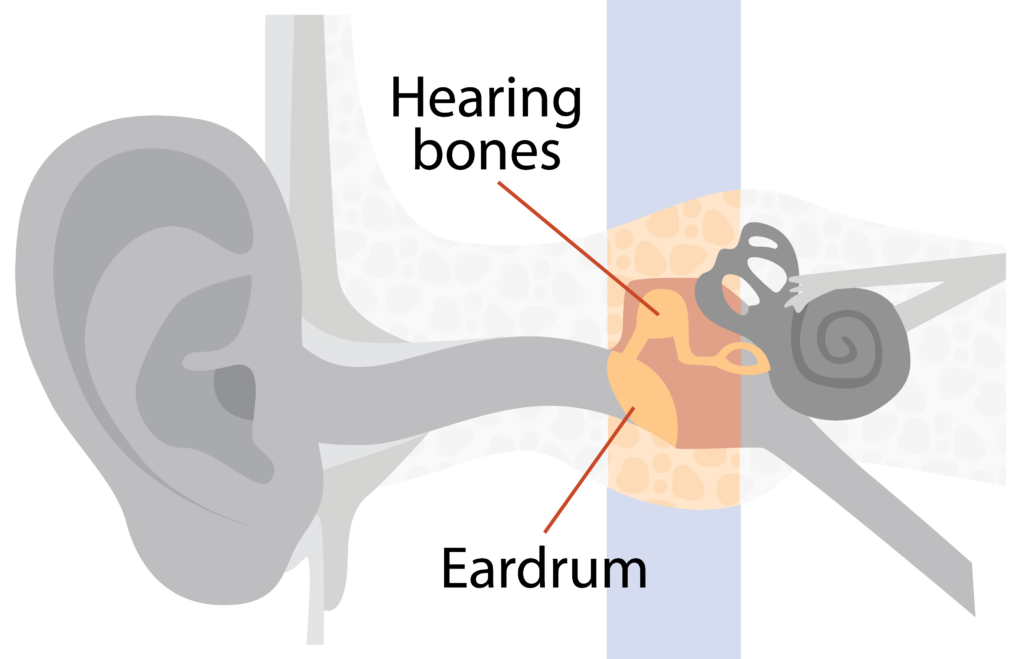

Middle ear

The middle ear is made up of the:

- Eardrum (tympanic membrane)

- Small hearing bones.

The eardrum separates the outer and middle ear.